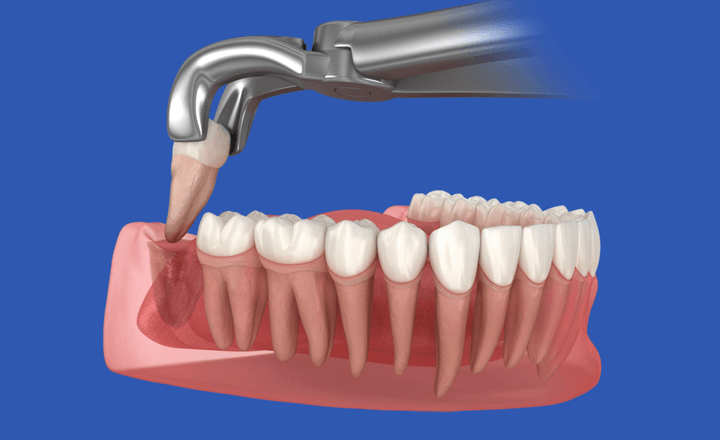

Навряд чи хтось дуже зрадіє, якщо стоматолог порекомендує видалення зубів . Але бувають ситуації, коли доводиться це зробити. У стоматологічному центрі White Clinic до такої процедури вдаються лише в крайніх випадках, коли інші методи лікування неможливі. Це означає, що спочатку дантисти намагаються зберегти зубну одиницю за допомогою сучасних технологій. Але якщо лікар все-таки запропонував екстракцію, варто бути готовим до того, що може очікувати після хірургічного втручання.